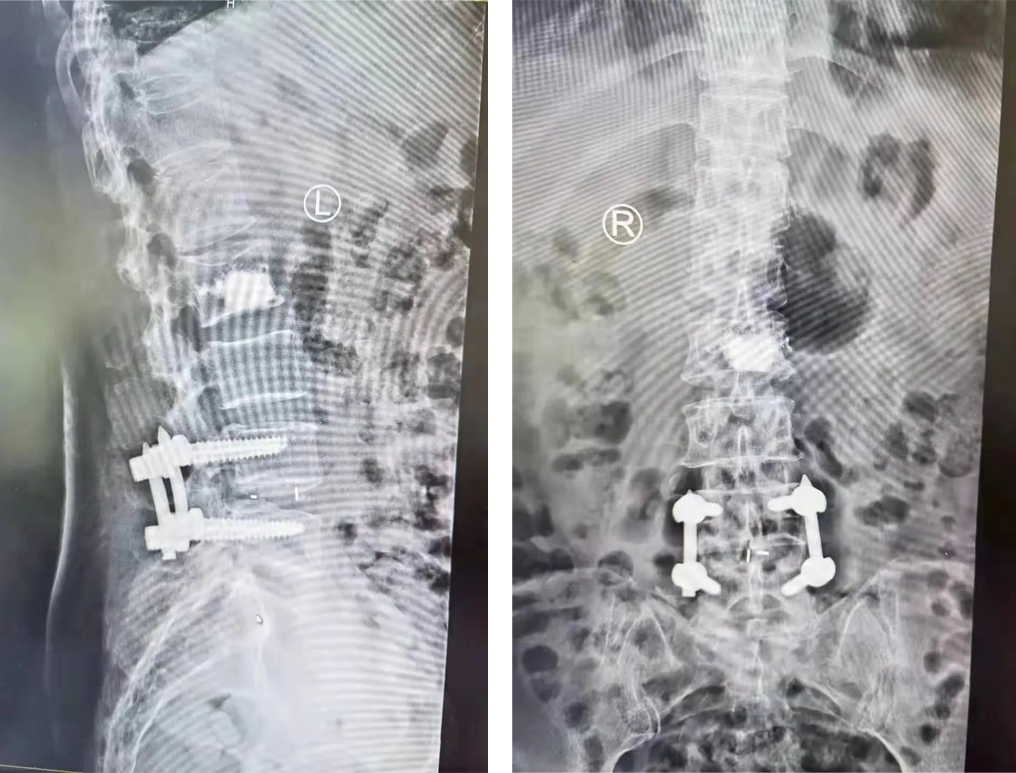

手术前

通过影像等相关检查,明确诊断:1、L2、L4椎体压缩骨折;2、L4/5腰椎椎管狭窄症。根据诊断确定手术方式。